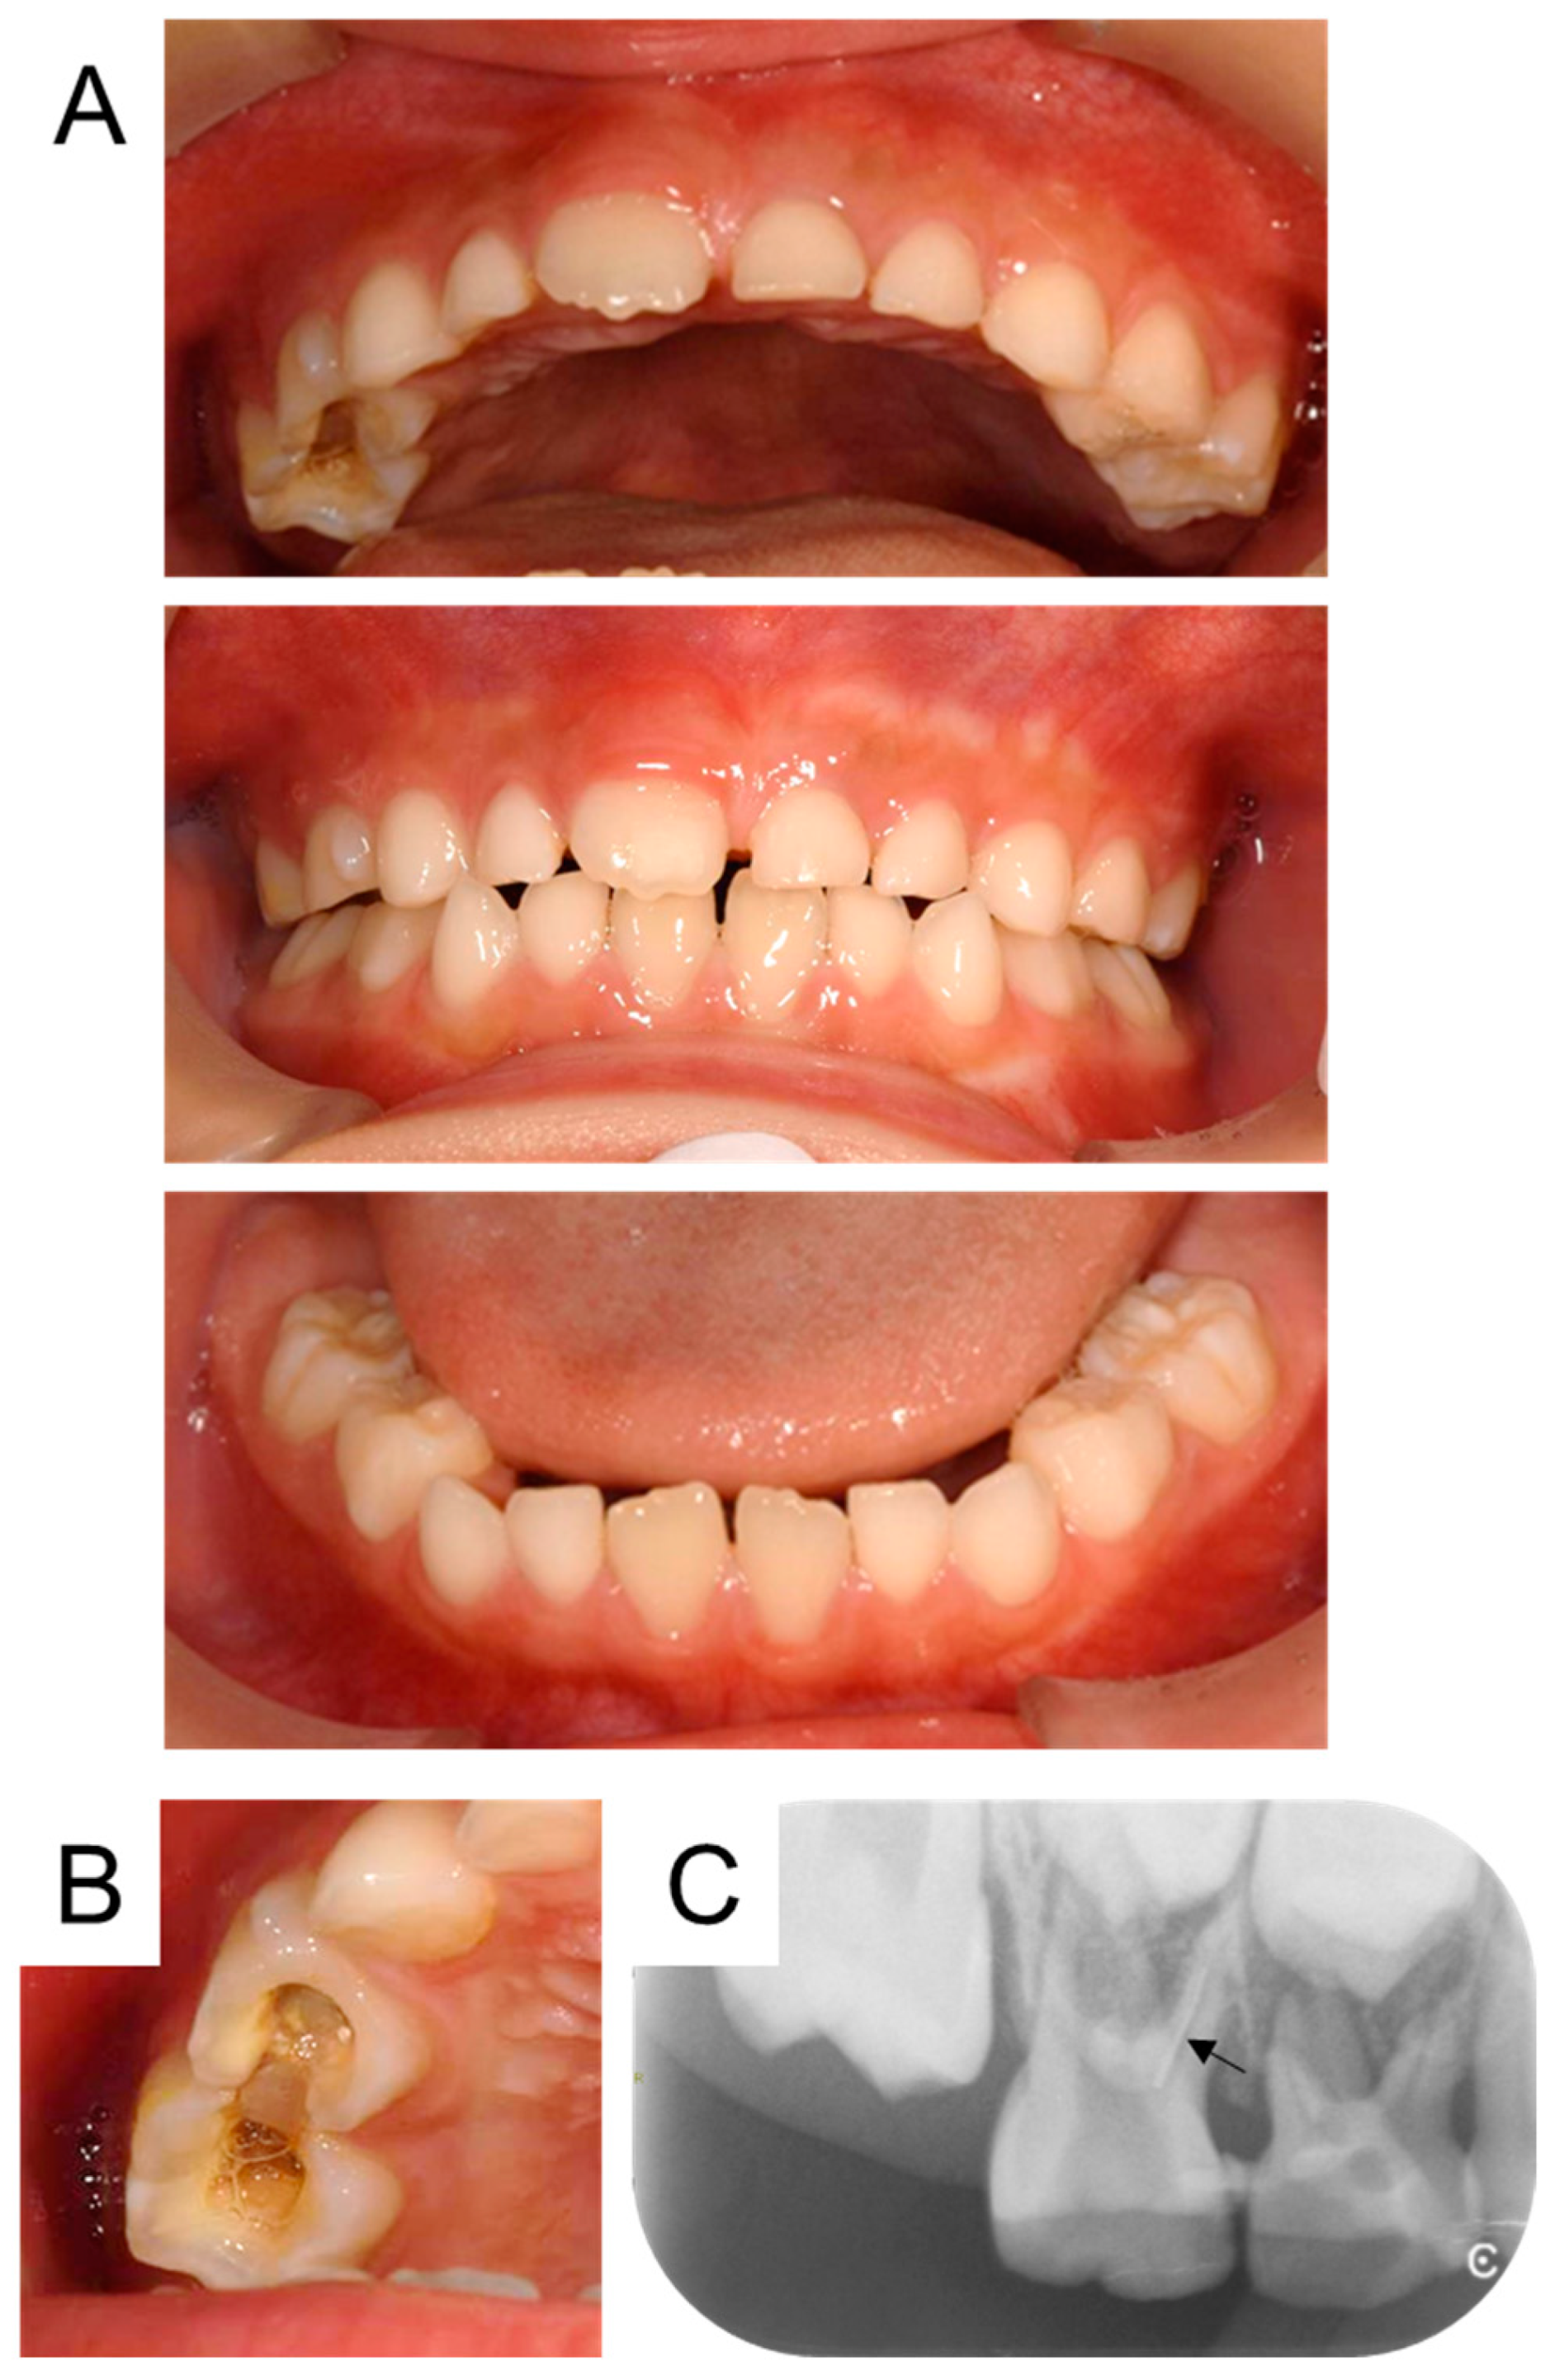

| Present case | #55 | Mesio-buccal canal | Reamer | 17 months | Enamel hypoplasia |